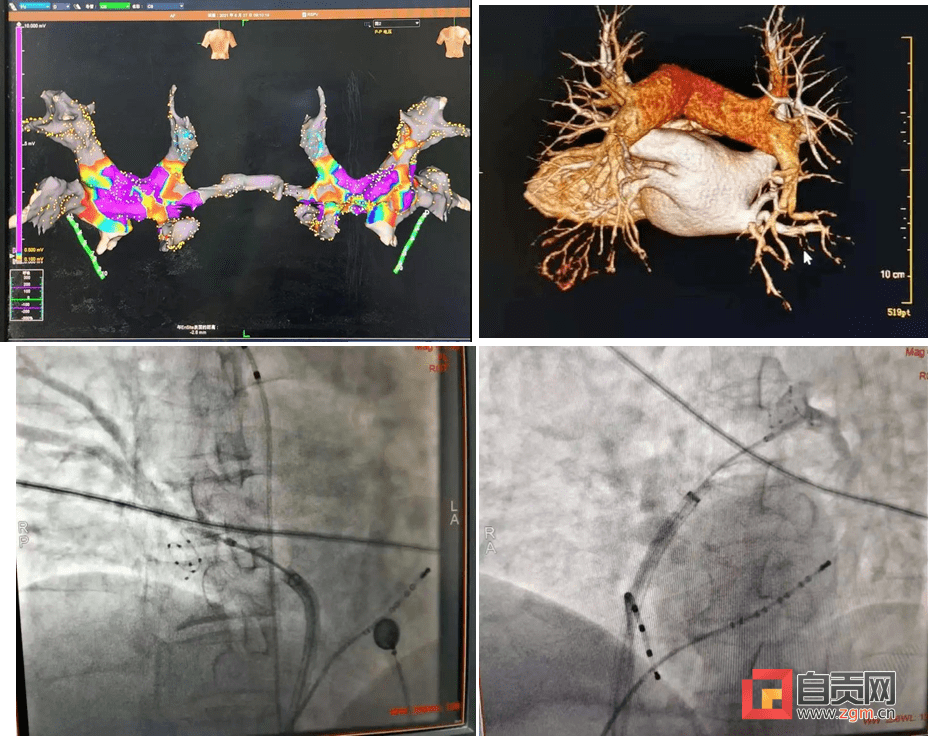

自贡一医院独立开展川南首例房颤冷冻消融术

图片尺寸928x738